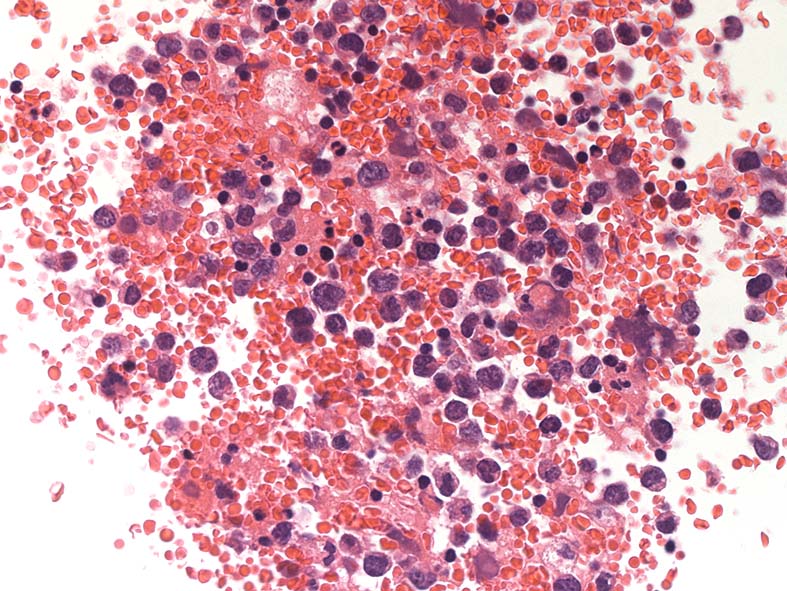

胸水セルブロック: effusion lymphomaの場合, IHCなどの精査はcell brockで行うことになる.

心嚢水セルブロックHE染色: 小リンパ球の3倍から5倍ほどの大型異型細胞が多数増加している. 核は類円形, くびれをもつ多型核が見られ, クロマチンは微細な傾向. 核小体を1-数個もつ.

N/C比は大. 好酸性の細胞質が認められる. セルブロックでは細胞質空胞はあまりめだたない. high-grade lymphoma疑い.